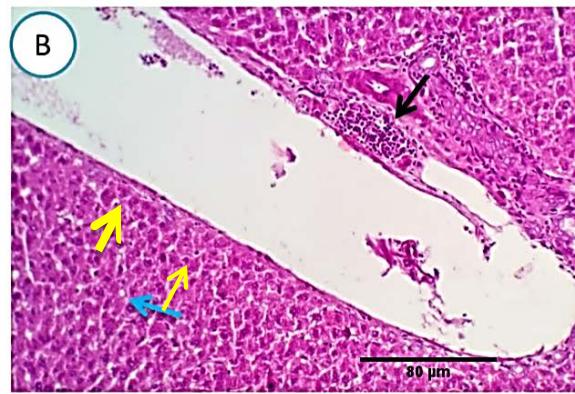

### d) Group 4 (Ginger protection followed by methomyl administration)

Liver: Sections from liver of this group denoted moderate portal biliary proliferation, congestion of portal blood vessels, round cell infiltration, multifocal interstitial lymphocytic and macrophages aggregations replacing previous necrotic patches beside degenerative changes in a few hepatocytes. (Fig.10)

Fig. 4: Photo-micrograph from liver, group (4), showing, portal biliary proliferation (A, yellow arrow, B, black arrow), congestions of portal blood vessels(A, black arrow), round cell infiltration and interstitial lymphocytic and macrophages aggregations replacing previous necrotic patches (B, blue arrow). Scale bars 120, 40, 40 um.